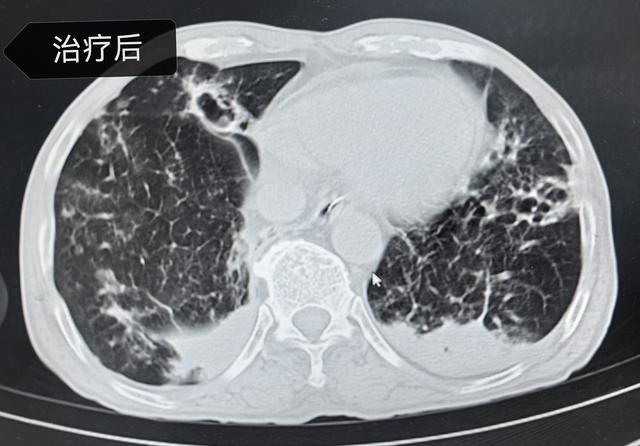

▲入院前和治疗后的肺部CT对比

科室主任李建民带领团队立即为姚大爷在科内组织疑难病例讨论,经过仔细询问病史及分析病情。经肺泡灌洗液的病原学检查,在其肺内找到了烟曲霉菌(真菌的一种)、肺炎链球菌(社区获得性肺炎的常见细菌)等病原体混合感染,通过积极的抗真菌、抗细菌、抗炎症反应、俯卧位等综合治疗,姚大爷最终转危为安,经过一段时间治疗,2月5日,姚大爷身体达到出院条件,待雨雪冰冻天气情况好转后返乡过年。